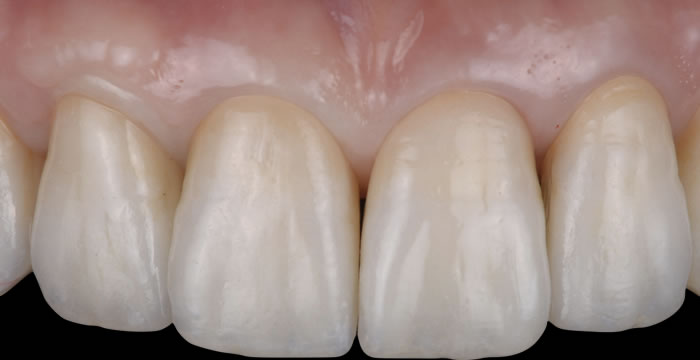

治療完了 |

骨も歯肉も回復しました。清掃性が良く、審美性に優れ、治療結果は十分な出来です。 |